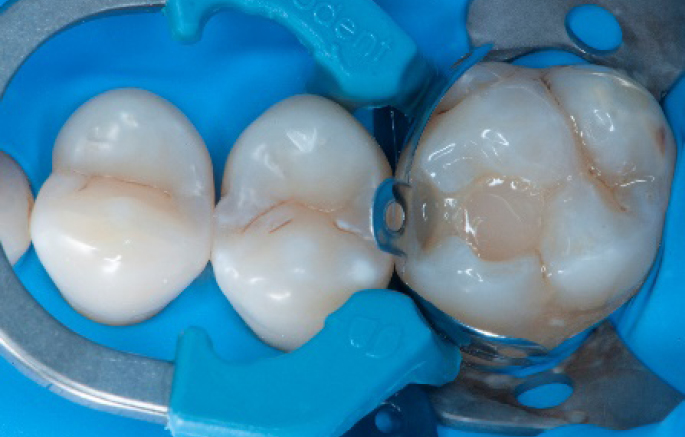

Step 6:

Selective enamel etching procedure with Conditioner2.

Step 7:

Adhesive application with a universal adhesive, Prime&Bond3.

Step 8:

Transformation of class II into class I, restoring the interproximal wall with Spectra ST4 composite in shade A2.

Step 9:

Transformation of a big class I into a small class I, using SDR® flow+ material in one increment up to 4 mm.

Step 10:

The situation after the application of SDR® flow+ material.